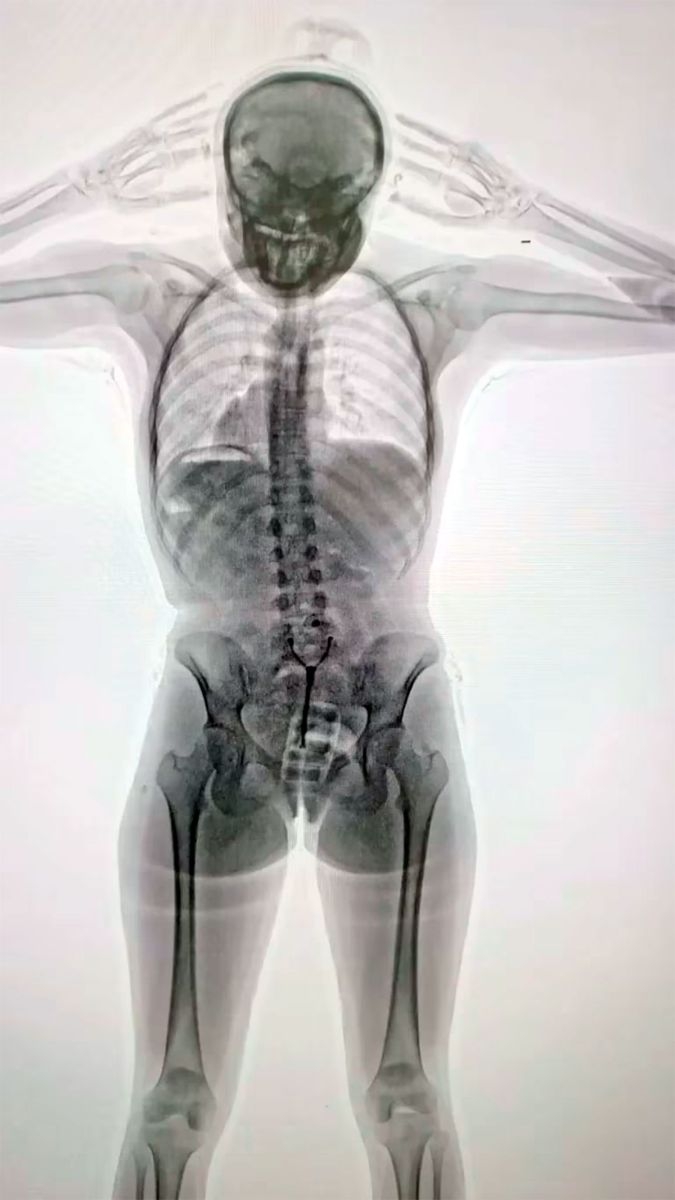

Imágenes son impactantes. La joven de 20 años que fue descubierta tras un control con equipo de rayos X en Ezeiza.

Una joven de 20 años fue detenida en los últimos días en el Aeropuerto Internacional de Ezeiza tras ser descubierta por las autoridades aeroportuarias cuando intentaba viajar a Europa con droga oculta dentro de su cuerpo: le encontraron más de 700 gramos de cocaína en su vagina y su estómago.

Ante las consultas, la pasajera “respondió de manera incongruente y dubitativa”, lo cual levantó aún más las sospechas. Ante esta situación, agentes de la Policía de Seguridad Aeroportuaria (PSA), conjuntamente con funcionarios de la Dirección General de Aduanas y personal de AIRCOP, procedieron a realizarle un control corporal no invasivo mediante equipo de rayos X (Body Scan) y delante de la presencia de testigos.

La inspección dio pie a la revelación del delito: en las imágenes los efectivos observaron la posible presencia de elementos extraños en el organismo, concentrados en su zona genital.

En consecuencia, con la orden judicial en mano, la pasajera empezó a ser requisada hasta que en un momento confesó espontáneamente y manifestó que transportaba un paquete introducido vía vaginal. Concretamente, había introducido en su cuerpo un profiláctico con 11 cápsulas de cocaína, de aproximadamente 10 gramos cada una.

Como parte del procedimiento, la joven fue trasladada al Hospital de Ezeiza. Allí, bajo custodia de la PSA, estuvo incomunicada mientras evacuaba las cápsulas detectadas en las imágenes del escáner, las cuales finalmente fueron muchas más que 11: tenía otras 67 cápsulas en el sistema digestivo. En total, en su cuerpo llevaba 742 gramos de esa droga.